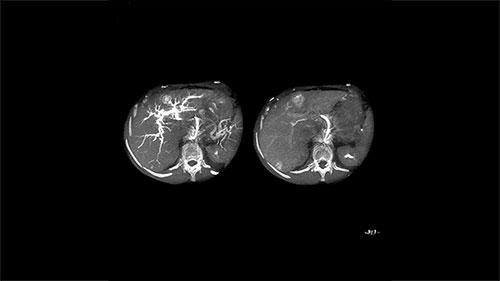

XperCT Dual allows two phases of a contrast injection to be displayed next to each other. Clinicians can assess the feeder vessels to a tumor in the arterial phase and see the tumor boundaries in the delayed phase. Studies have shown that this novel method is superior to conventional DSA and provides equivalent imaging information to the gold standard of contrast enhanced MRI.³ ⁶

XPERCTDUAL 6 LM